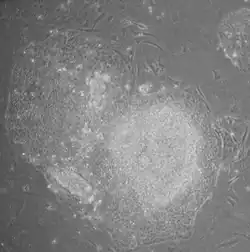

iPSC derivation is typically a slow and inefficient process, taking one–two weeks for mouse cells and three–four weeks for human cells, with efficiencies around 0.01–0.1%. However, considerable advances have been made in improving the efficiency and the time it takes to obtain iPSCs. Upon introduction of reprogramming factors, cells begin to form colonies that resemble pluripotent stem cells, which can be isolated based on their morphology, conditions that select for their growth, or through expression of surface markers or reporter genes.

- Morphology: iPSCs were morphologically similar to ESCs. Each cell had round shape, large nucleolus and scant cytoplasm. Colonies of iPSCs were also similar to that of ESCs. Human iPSCs formed sharp-edged, flat, tightly packed colonies similar to hESCs and mouse iPSCs formed the colonies similar to mESCs, less flat and more aggregated colonies than that of hESCs.